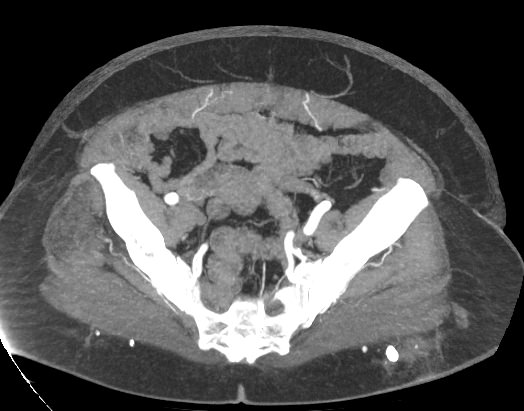

При нативной КТ кровеносные сосуды не видны. Поэтому, чтобы детально визуализировать сосудистую систему, обязательно проводится контрастное усиление. Для этого в периферическую вену пациенту вводится контрастный препарат, который попадая в кровеносное русло, поглощает рентгеновские лучи и ярко контрастирует сосудистую систему малого таза. В результате получаются детализированные снимки кровоснабжения внутренних половых органов, мочевого пузыря, прямой кишки.

На снимках КТ-ангиографии с контрастированием четко видна брюшная аорта, место ее разветвления на подвздошные артерии (бифуркация), а также сосудистые ветви, отходящие к органам малого таза. Снимки и 3D-изображения позволяют оценить: